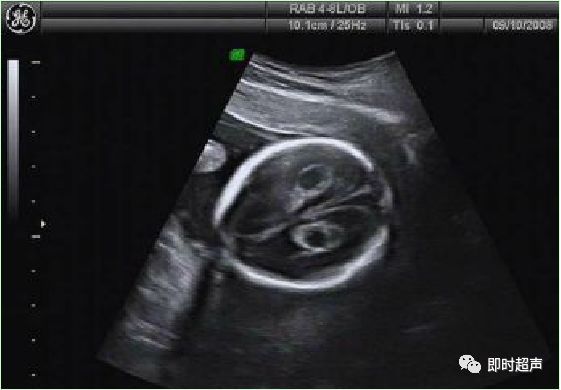

脉络丛囊肿CPC 是指孕 14 ~ 28周经超声检查在胎儿侧脑室脉络丛内发现的散在的直径≥2mm 的小囊肿。

✔ CPC发生率1%-2%,正常胎儿可一过性出现。

✔ 声像图为在均质强回声的脉络膜丛内见到圆形或椭圆形无回声结构,多为3-5mm大小。

✔ 单纯CPC中染色体异常的机率在1%-2.4%。

✔ 妊娠26-28周左右95%以上的CPC逐渐消失。

✔ 大约有1-3%的正常人群中在中期妊娠的超声检查中可发现有CPC。有建议5mm以下不报告。

✔ 如果囊肿小于1cm或越来越小,染色体异常可能性小。

✔ 囊肿大于 1 cm 时,约 1% ~2%有胎儿染色体异常,这些胎儿大部分都有另外的畸形。以 18 、21-三常见。

✔ 胎儿脉络丛囊肿作为产前超声诊断中的超声标记之一,可以提示胎儿染色体异常的风险性。

✔ 囊肿较大或胎儿合并其他畸形时应做胎儿染色体检查。